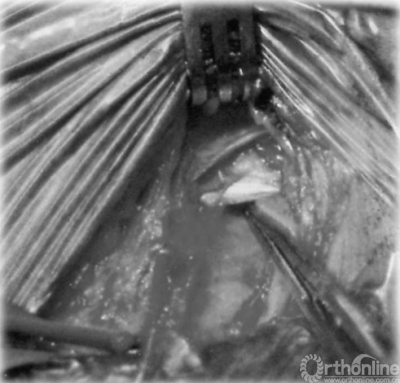

神经松解手术